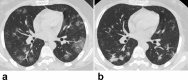

Findings: Compared with the non-pregnant adults group (n = 14), initial normal body temperature (9 [56%] and 16 [64%]), leukocytosis (8 [50%] and 9 [36%]) and elevated neutrophil ratio (14 [88%] and 20 [80%]), and lymphopenia (9 [56%] and 16 [64%]) were more common in the laboratory-confirmed (n = 16) and clinically-diagnosed (n = 25) pregnant groups. Totally 614 lesions were detected with predominantly peripheral and bilateral distributions in 54 (98%) and 37 (67%) patients, respectively. Pure ground-glass opacity (GGO) was the predominant presence in 94/131 (72%) lesions for the non-pregnant adults. Mixed consolidation and complete consolidation were more common in the laboratory-confirmed (70/161 [43%]) and clinically-diagnosed (153/322 [48%]) pregnant groups than 37/131 (28%) in the non-pregnant adults (P = 0·007, P < 0·001). GGO with reticulation was less common in 9/161 (6%) and 16/322 (5%) lesions for the two pregnant groups than 24/131 (18%) for the non-pregnant adults (P = 0·001, P < 0·001). The pulmonary involvement in children with COVID-19 was mild with a focal GGO or consolidation. Twenty-three patients underwent follow-up CT, revealing progression in 9/13 (69%) at 3 days whereas improvement in 8/10 (80%) at 6-9 days after initial CT scans.

Interpretation: Atypical clinical findings of pregnant women with COVID-19 could increase the difficulty in initial identification. Consolidation was more common in the pregnant groups. The clinically-diagnosed cases were vulnerable to more pulmonary involvement. CT was the modality of choice for early detection, severity assessment, and timely therapeutic effects evaluation for the cases with epidemic and clinical features of COVID-19 with or without laboratory confirmation. The exposure history and clinical symptoms were more helpful for screening in children versus chest CT.